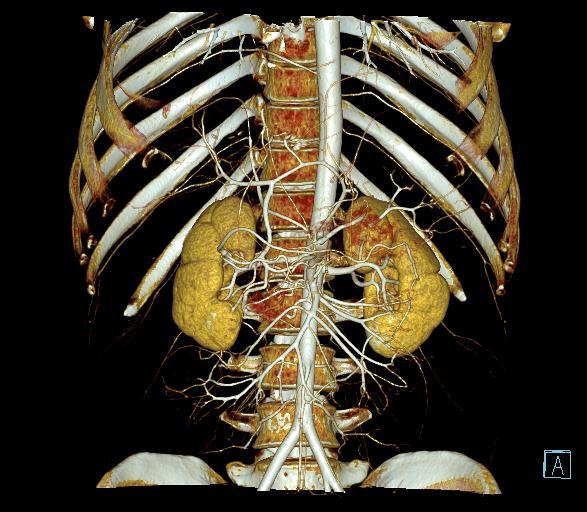

图 3:肝动脉显影(VRT/MIP)

图 6:肝动脉 VRT 图